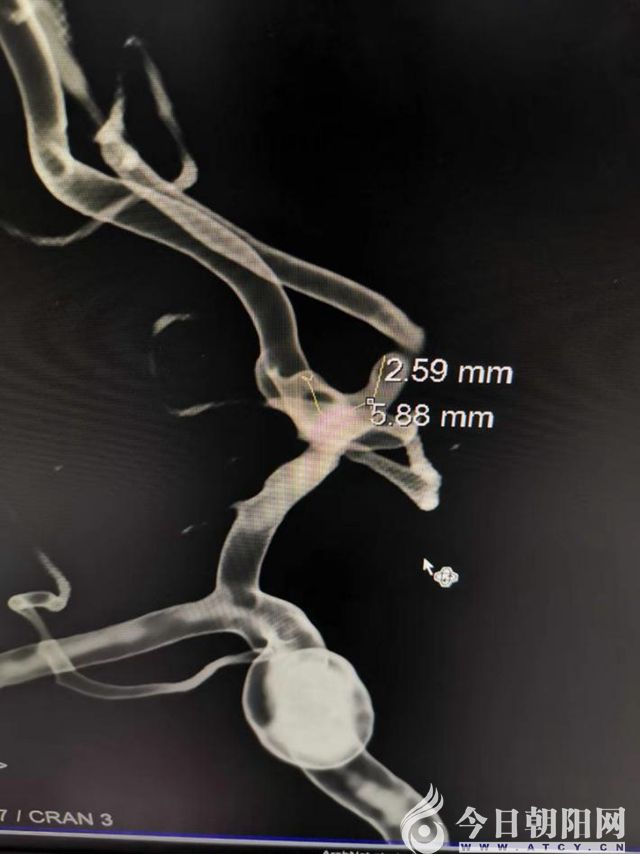

3D—DSA成像

3D—DSA成像內(nèi)徑測(cè)量